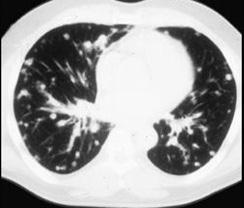

问题 女,72岁,咳嗽,胸闷,呼吸困难1月余,1年前行结肠癌根治术,CT检查如图,请选择最可能的诊断 ( )

选项 A、间质性肺炎 B、粟粒型肺结核 C、肺转移瘤 D、尘肺 E、肺癌

答案 C